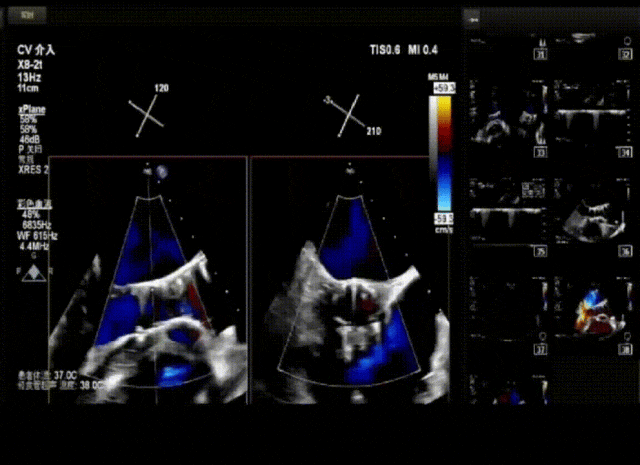

患者病史 男性,74y, 因 “发现心脏瓣膜病 1 年,加重伴喘气半年” 入院。门诊检查显示主动脉瓣重度AS并伴轻-中度AR。患者基础疾病较多:胸腹主动脉多发穿透性溃疡、心功能III级等,手术指征明确,但风险极高。 术前CT LVOT- Annulus 倒梯形,对植入瓣膜有挤压位移风险,Annulus直径23.7mm,瓣叶增厚,钙化集中在无冠窦边缘。 左冠脉开口高度可,瓣叶不长、窦部空间较大,无冠脉风险;室间隔膜部较短,有一定PPI风险,心脏角度37.9°;心室较小,有一定循环崩溃风险,术前注意补液。 术前造影角度及入路:血管入路散在钙化、无迂曲;主动脉弓条件好、双侧股动脉直径大、右股穿刺点侧壁存在环形钙化 左右重合位:RAO 7° CAU 21° 右窦中心位:LAO2 1° CAU 1° 手术策略 20mm球囊预扩后植入AV26瓣膜,同时做好预防循环崩溃、传导阻滞的应急预案。 术中挑战 1)球囊预扩:20mm球囊预扩时无明显 “腰征”,但存在少量反流,提示瓣膜钙化与解剖结构对扩张的阻力不均 2)首次释放偏差:第一次定位释放时,瓣膜在 “开花” 过程中下滑约 3mm,工作位观察显示小弯侧瓣周漏较多(深度超过完全覆膜区),需二次调整。 3)二次精准定位:以猪尾导管为参照,将定位点调整至 “猪尾 - 2mm” 处,结合真实窦底深度(较深)重新释放,最终瓣膜位置稳定,瓣周漏显著减少。 术后即刻效果: 瓣膜形态良好,跨瓣压差从术前的 67mmHg 降至 6mmHg,且无明显瓣周漏,冠脉开口通畅; Commisural Alignment 术后即刻超声: Prostyle A®预装干瓣——助力临床最优化解决方案: √ 平衡的径向支撑力:特殊的解剖结构下位置形态良好,术后跨瓣压差大幅降低,血流动力学改善明显; √ 80%可回收设计:支持术中二次调整释放位置,保证精准释放; √ 平衡的收腰设计&Commissural Alignment设计: 为患者后期冠脉PCI保留了生命通道;